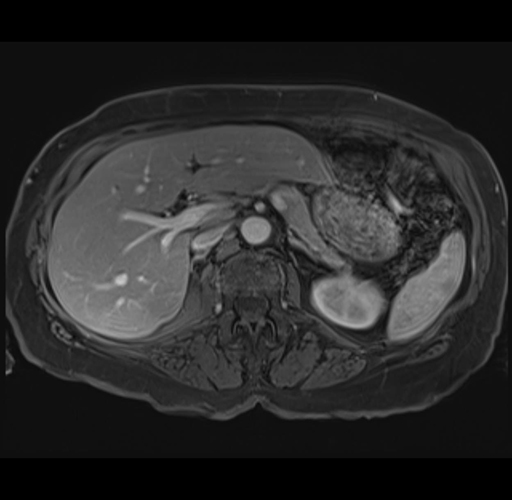

MRI T1